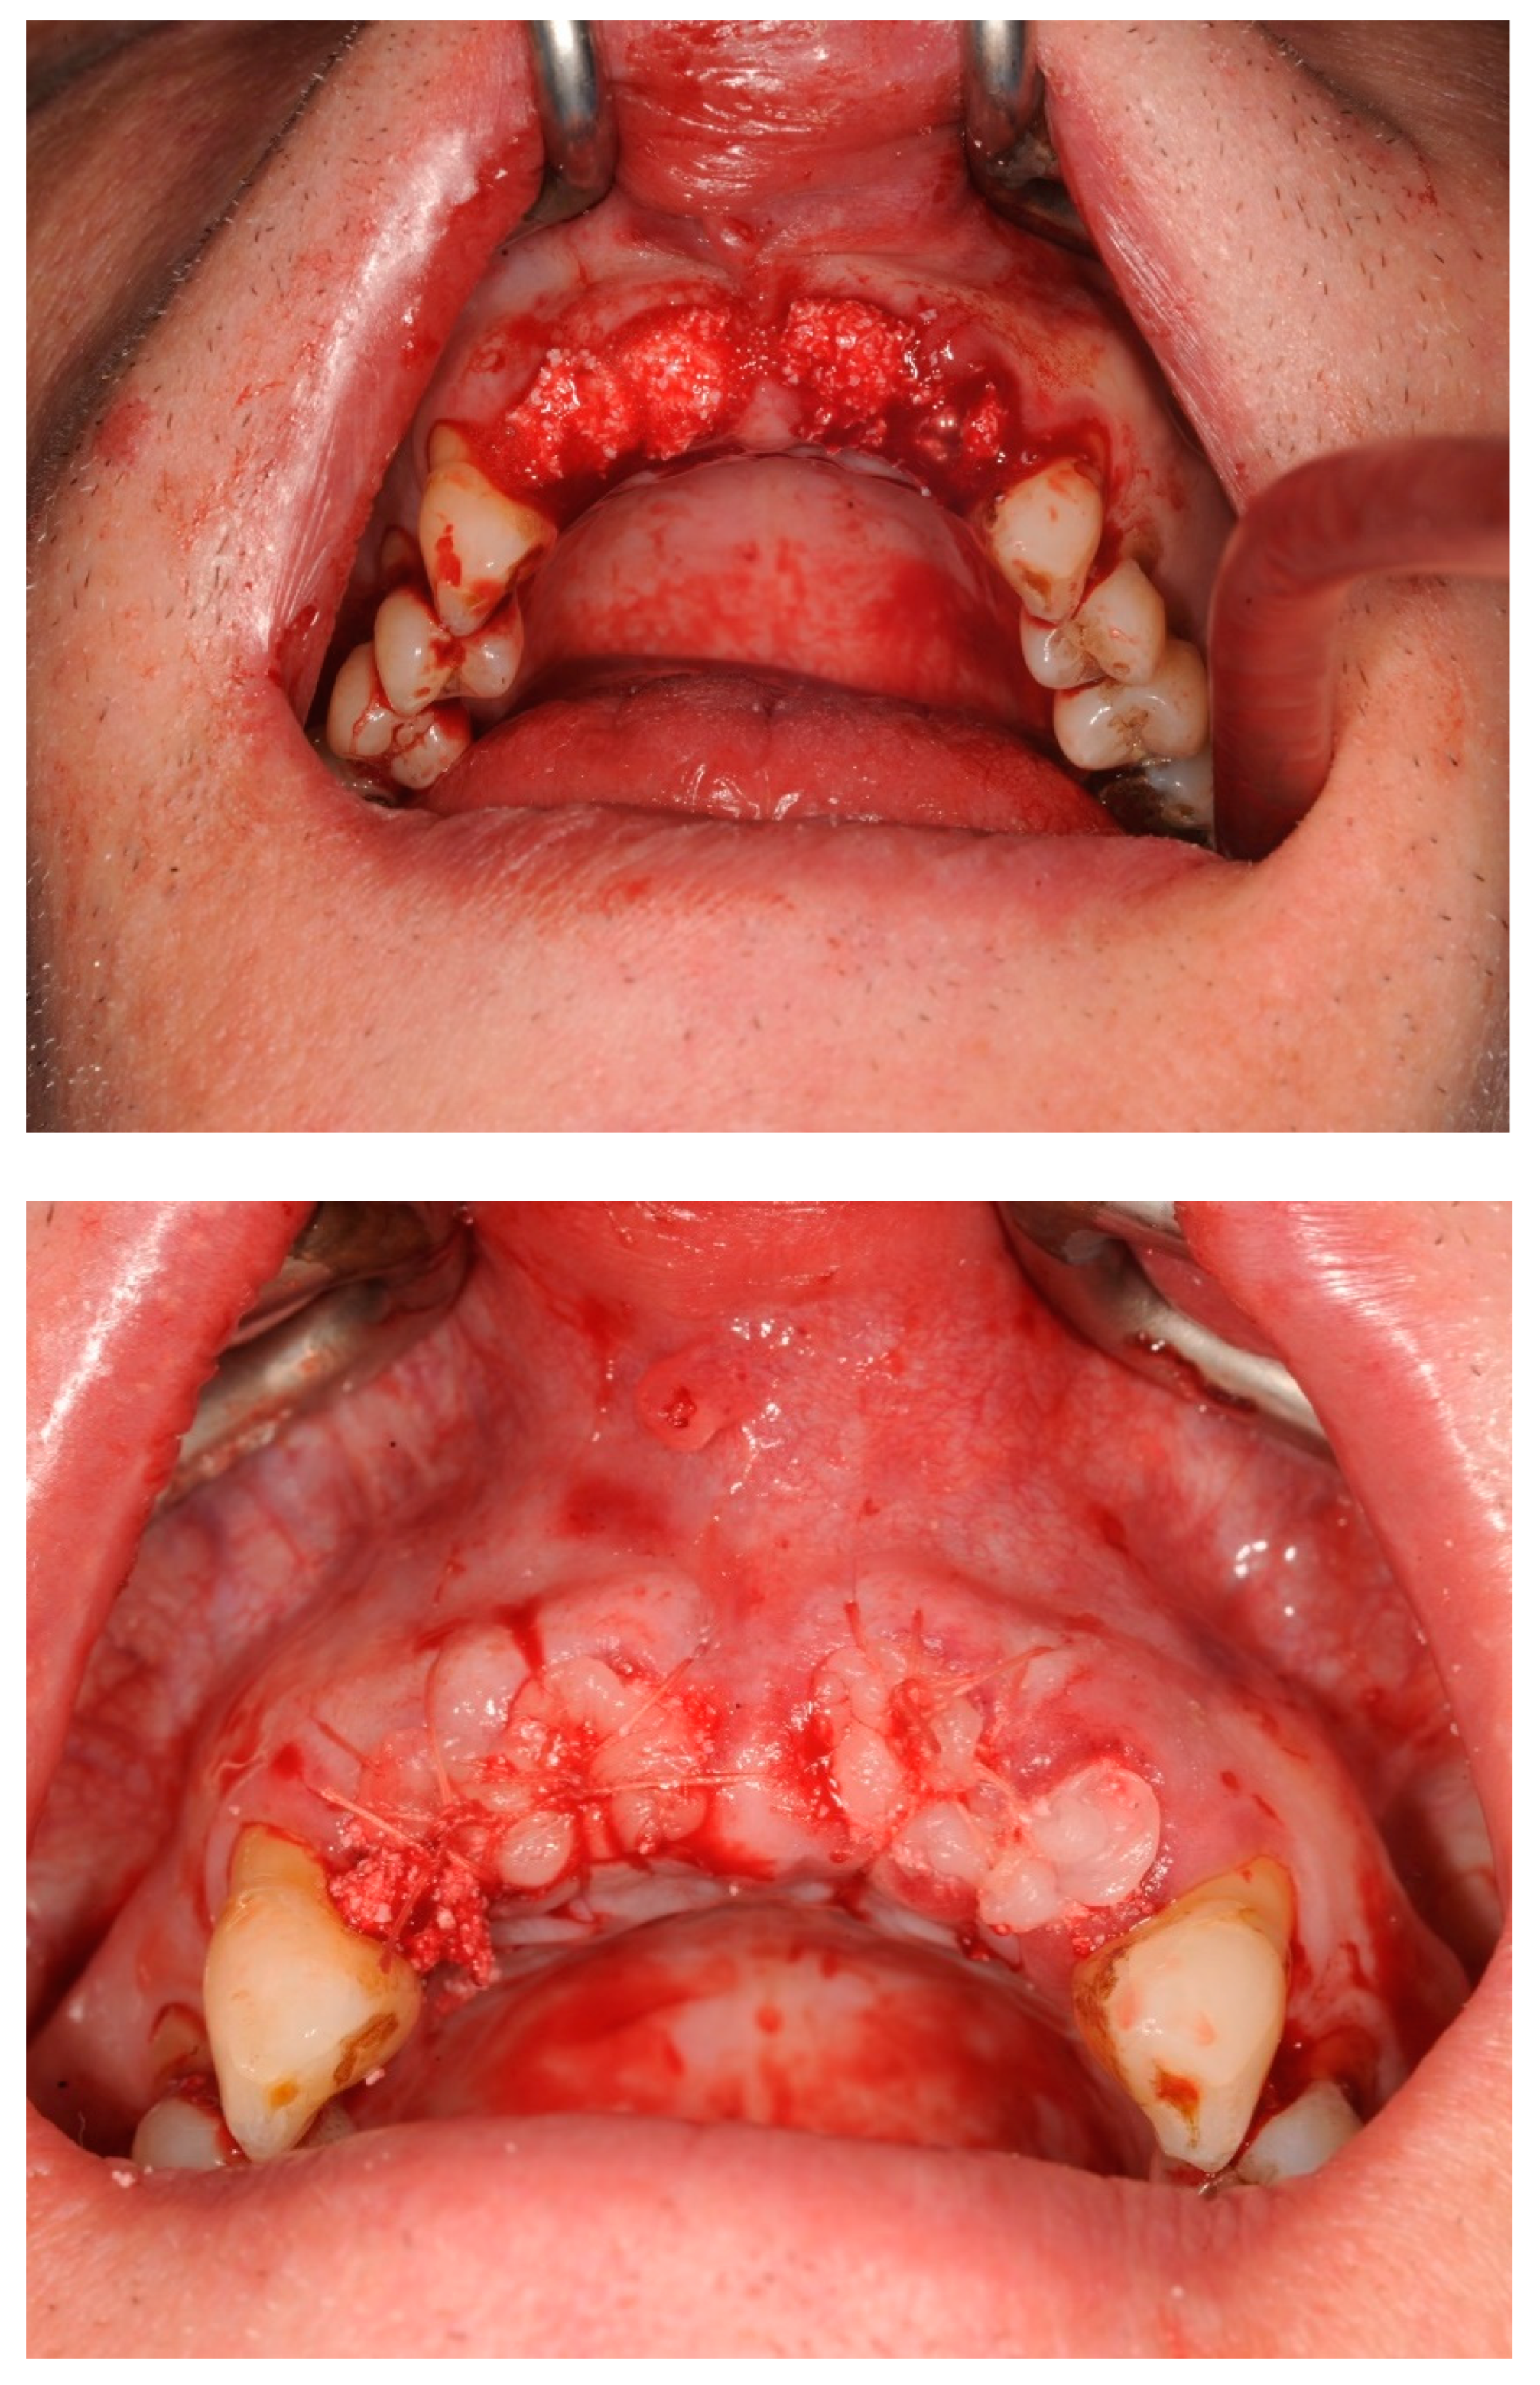

- Step 3: Teeth were removed using a minimally invasive extraction technique and the sockets were grafted with a xenograft and PRF

2.2. Alveolar Ridge Preservation Technique

3.1. Case Study 1

3.2. Case Study 2

| Case 1 | 60, male, prediabetes, non-smoker with no medication | open ARP | Full contour preserved | excellent | high | D2-3 | None | 8 weeks | 6 weeks | No crestal bone loss |

| Case 2 (implant 1) | 55, female, hay fever, non-smoker | open ARP | Full contour preserved | excellent | high | D2-4 | None | 9 weeks | 7 weeks | No crestal bone loss |

| Case 2 (implant 2) | 55, female, hay fever, non-smoker | open ARP | Full contour preserved | excellent | high | D2-4 | None | 9 weeks | 8 weeks | No crestal bone loss |